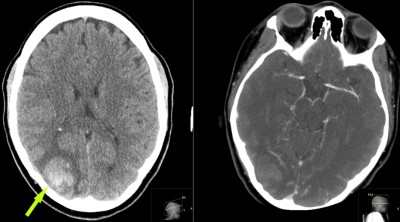

This is a 24 year old female who presented to the ER 2 years prior with first time seizure.

She is admitted to hospital, evaluated, and released.

She did not follow-up with neurosurgery at that time.

One year later, again presents to ER with another seizure; undergoes work-up and is again released.

6 months later she follows up with neurosurgeon.

She has mild, intermittent visual disturbance